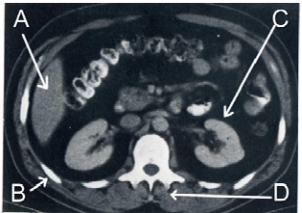

33 如圖所示,有關此電腦斷層之各部位解剖結構之判讀,下列何者正確?

①A 為肝臟 ②B 為肋骨 ③C 為右腎 ④D 為神經根 (A)①② (B)①④ (C)②③ (D)③④